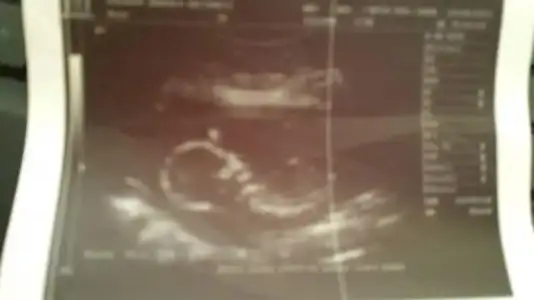

Eki Görüntüle 776534

Eki Görüntüle 776535

Eki Görüntüle 776536

kızlar benim resimlerede bi yorum yapın ne acaba?ben anlayamadım.çabuk yazın çok merak ediyorum![]()

hayret bu resme gore kiz dr erkek demis gerci resim tamda net degil allhim tamamina erdirsin